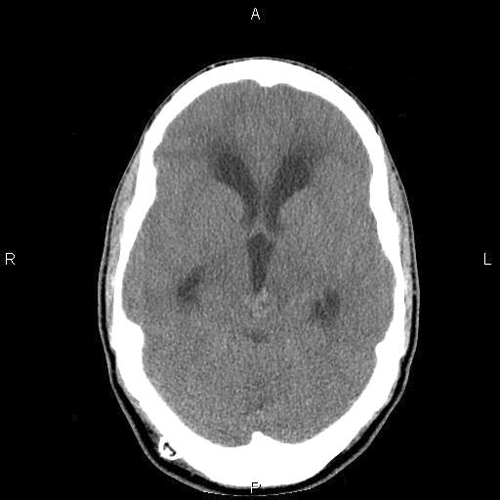

A poorly defined lesion is identified in the pineal region of the CT scan. The increased density suggest calcifications (Panel A). A moderate degree of hydrocephalus is also present (Panel B).

On MRI studies, pineal germinomas and primary pineal tumors are usually isointense to gray matter on T1-weighted, are slightly hyperintense on T2, and have strong homogenous enhancement. Intratmuoral cysts can occur as well. CT scan shows the lesion as a hyperdense mass that surrounds a calcified pineal gland. The neuroimaging characteristics of germinomas and nongerminomatous germ cell tumors are similar enough to limit diagnostic certainty, and either tissue confirmation or the measurement of specific tumor markers is needed for diagnosis. Pineal calcification on plain radiographs, uncommon in children less than 10 years of age, is a useful clue to the diagnosis of a germ cell tumor, since approximately 70% of patients with pineal region tumors have calcifications 1. The calcifications in germinoma surround the pineal gland as the germinoma grows. In contrast, pineocytomas commonly have intratumoral calcifications. Unlike germinomas, teratomas typically have heterogenous MRI signals because they can contain tissue from all 3 germinal layers.